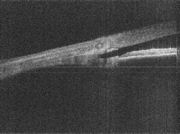

A team at Duke University has shown for the first time that a full-range Fourier-domain optical coherence tomography (FDOCT) system can provide high-speed high-resolution in vivo imaging of the eye's anterior drainage chamber.

FDOCT systems operating at a central wavelength of 1310 nm have been tried in glaucoma diagnosis before, but the increased sensitivity of the Fourier-domain approach comes at the price of limited usable imaging depth, partly due to the presence of a symmetric overlapping image artefact in the images. This artefact, referred to as the complex conjugate artefact, complicates image acquisition and prevents the technique from looking deeper than 3 to 4 mm into the critical anterior chamber of the eye; not deep enough for a firm diagnosis.

"Resolution of the complex conjugate artefact permitted a scan depth in excess of 6.3 mm, allowing imaging of the entire depth of the anterior chamber while reducing artefacts," said Asrani. "The combination of this depth resolution and the detailed viewing possible with FDOCT technology represents a novel breakthrough in this field."